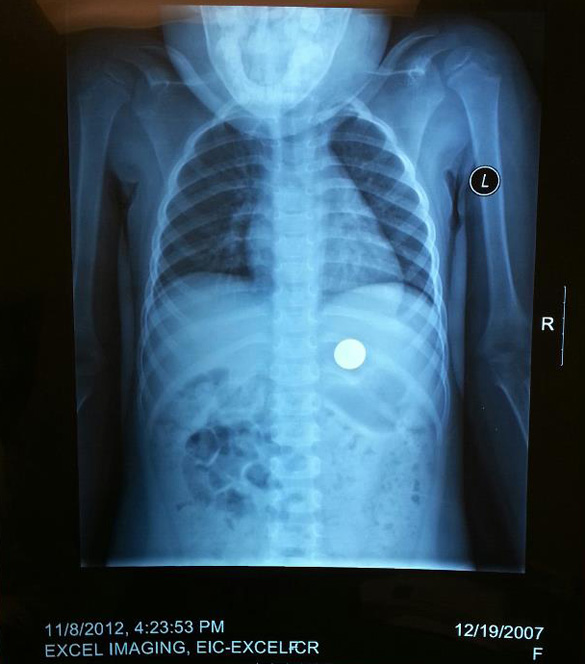

Yesterday, Audrey swallowed a dime at her sitter's. She only told her sitter she had a tummy ache. So I had the sitter drop her off with my mom and then I arrived home about two minutes later. She had already confessed to grandma. The pediatrician told us to come in and they'd take an xray to make sure it wasn't lodged in her windpipe. So this weekend, we'll be waiting for change, so to speak. Gross. I learned that the poison control gets over 92,000 calls a year about kids swallowing coins. I get ill when I think of her choking. We are so lucky.